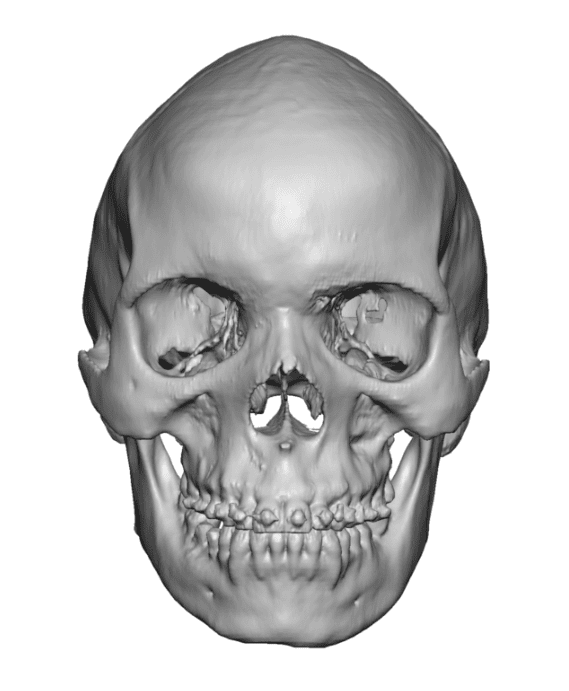

Desire for change of head shape from front view form an inverted V shape to a rounder and wider head shape.

Placement of custom extended forehead-temporal implants through incisions in the crease behind the ear. (he had a prior back of head skull implant which is green in the implant designs and which the head widening implants partially covered it)

Desire for change of head shape from front view form an inverted V shape to a rounder and wider head shape.

Placement of custom extended forehead-temporal implants through incisions in the crease behind the ear. (he had a prior back of head skull implant which is green in the implant designs and which the head widening implants partially covered it)